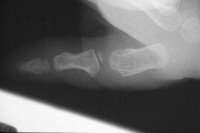

| Case 3. Wassell II duplication of the distal phalanges, reconstructed with proximal phalanx head narrowing, closing wedge osteotomy and radial collateral ligament reconstruction from the deleted segment. |